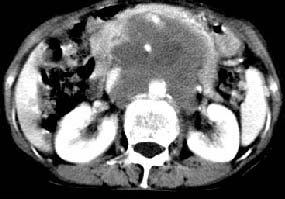

ct:肝胃之间、胰头后、腹主a周围,融合而成团块状影,包绕血管,胰腺前移后缘分界欠清,与肝胃分界清,肿块未见明显强化,肝右叶后段小囊肿。

女:61岁.腹痛腹胀20天,行b超腹膜后实性占位.扫完后我查体发现患者右颈根部约3厘米类圆性包块,有移动{考虑右颈根部包块是肿大淋巴结}.

诊断:淋巴瘤>转移瘤。

肝胃之间、胰头后、腹主a周围,融合而成团块状影,包绕血管,胰腺前移后缘分界欠清,与肝胃分界清,肿块未见明显强化,考虑淋巴瘤可能性大

胰腺受压前移,胰管扩张,应为腹膜后占位,病灶密度不均,有低密度坏死区,强化扫描强化不明显腹腔干动脉受侵,考虑腹膜后恶性占位

从发病部位(腹主动脉周围)及增强方式(均匀轻度强化、少量坏死)和病变形态(较大、多结节形)符合腹膜后淋巴瘤,建议颈部病变活检。

肝胃之间、肝十二指肠韧带,胰头后、腹主a周围,融合而成团块状影,包绕血管[腹腔干、肠系膜上动脉,腹主动脉],胰腺前移后缘分界欠清,与肝胃分界清,肿块未见明显强化,肝右叶后段小囊肿。

考虑1淋巴瘤。2转移瘤。3恶性组织细胞瘤。

主动脉-胰腺间隙可见巨大分叶状软组织肿块影,包绕腹主动脉、腹腔干及其分支、腔静脉等大血管,增强呈无明显强化,临近脏器明显受压移位,增强示有分界。肝右叶可见局限性低密影,边缘清楚。

考虑腹膜后淋巴瘤。